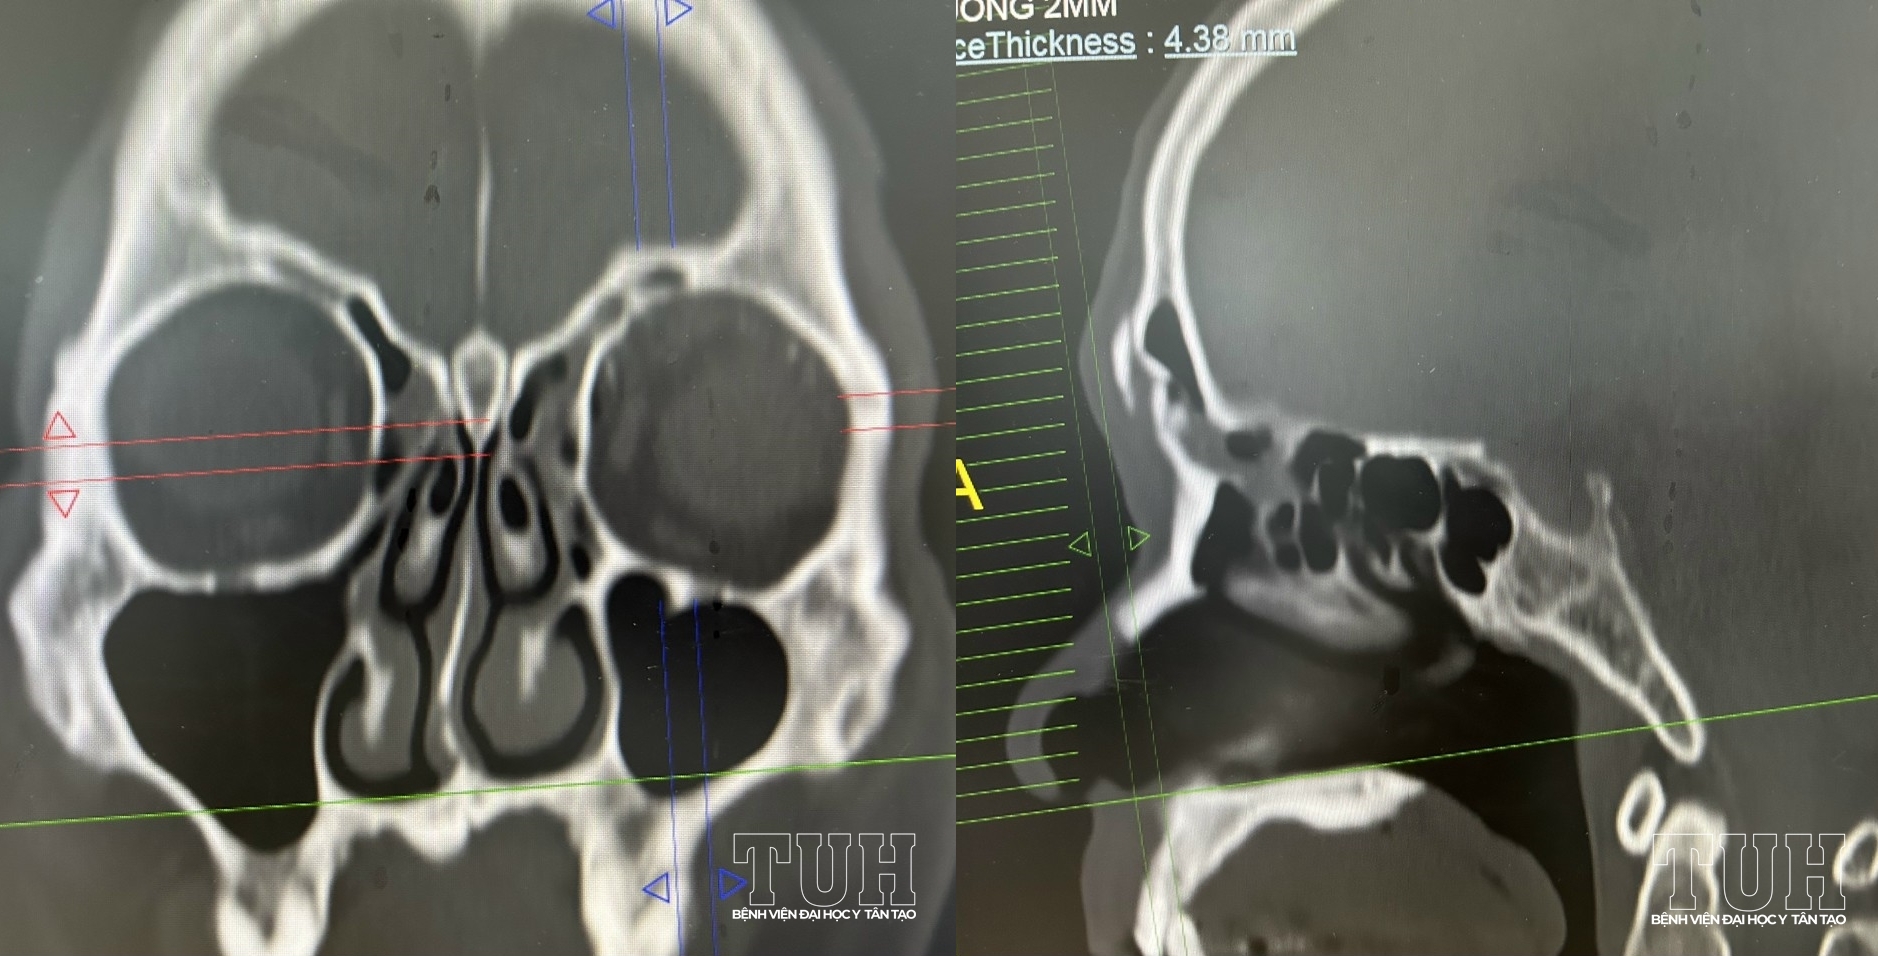

Ngày 26/4, Bệnh viện Đại học Y Tân Tạo cấp cứu nan nhân V.H.T trong tình trạng vỡ hở thành trước xoang trán do tai nạn lao động.

Sau khi đánh giá tổn thương phối hợp hội chẩn liên khoa, bệnh nhân được đánh giá thành sau và trần sàng nguyên vẹn, khớp mũi trán không gãy, không đặt dẫn lưu ngách trán vì không ảnh hưởng đến ống mũi trán.